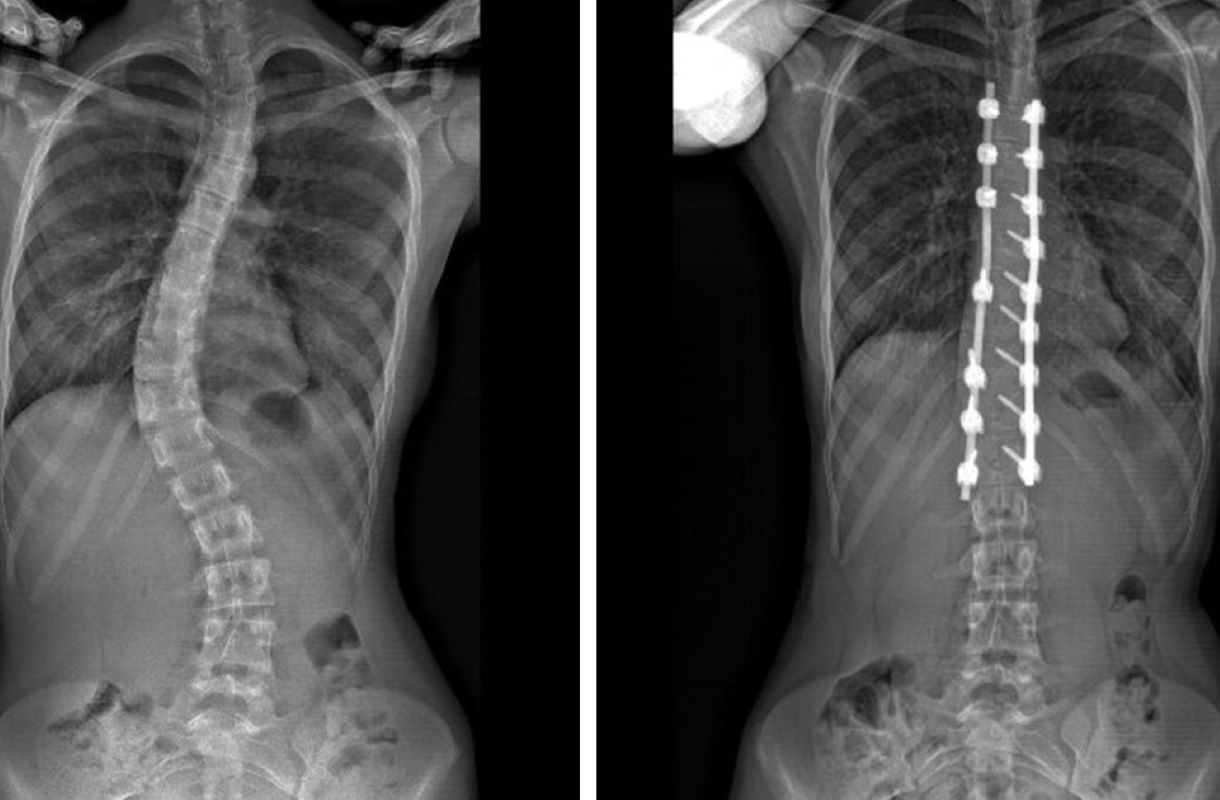

Kelainan tulang belakang yang ditandai dengan lengkungan abnormal. (Pedriatic The Orthopedic Center)

JawaPos.com–Skoliosis, kondisi kelainan pada tulang belakang yang menyebabkan kelengkungan abnormal, kini semakin banyak dialami berbagai kalangan. Penyakit ini tidak hanya dapat mempengaruhi penampilan fisik, tetapi juga dapat memengaruhi kualitas hidup pengidapnya.